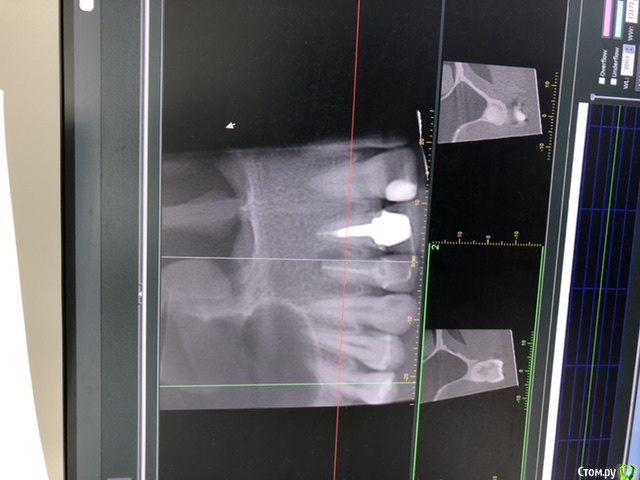

Лора777 Опубликовано 13 ноября, 2020 Автор Поделиться Опубликовано 13 ноября, 2020 Здравствуйте!Клкт посмотрите пожалуйста Ссылка на комментарий

Лора777 Опубликовано 13 ноября, 2020 Автор Поделиться Опубликовано 13 ноября, 2020 Клкт Ссылка на комментарий

Nazim_NV86 Опубликовано 13 ноября, 2020 Поделиться Опубликовано 13 ноября, 2020 До полости носа и синуса далеко. Изменения небольшие. Не вижу состояния синуса. покажите КЛКТ лору. Не можем ответить на вопрос об аллергии, т.к. нет данных про то, ложили что-то туда или нет( а если узнаем, то проверять наличие аллергии у аллерголога). Если этот зуб и виновен в рините, то только рефлекторно. Проверить это можно только его удалением (к сожалению). Ссылка на комментарий